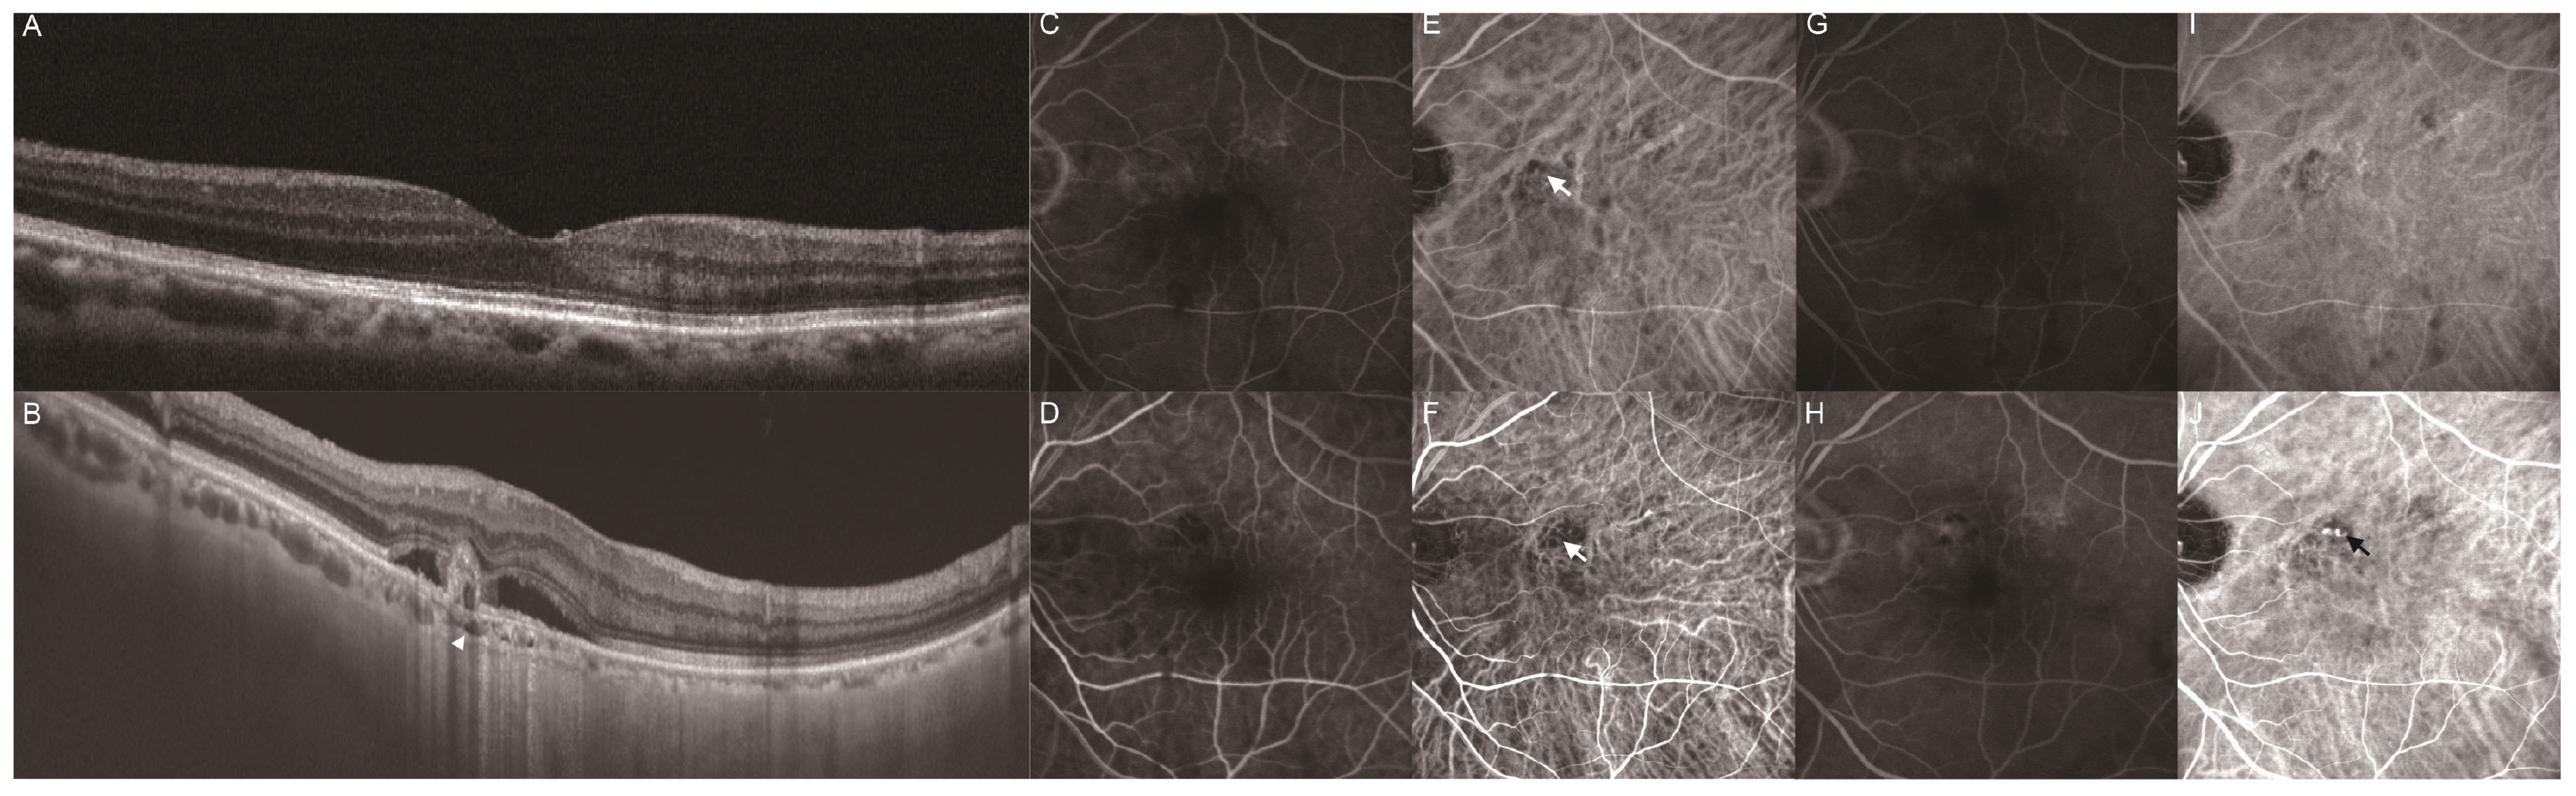

Clinical Characteristics of Punctate Hyperfluorescence Spots in the Fellow Eye of Patients with Unilateral Macular Neovascularization with No Drusen

- Tsujikawa, A.; Ojima, Y.; Yamashiro, K.; Ooto, S.; Tamura, H.; Nakagawa, S.; Yoshimura, N. Punctate hyperfluorescent spots associated with central serous chorioretinopathy as seen on indocyanine green angiography. Retina 2010, 30, 801–809. [Google Scholar] [CrossRef] [PubMed]

- Park, S.J.; Kim, B.H.; Park, K.H.; Woo, S.J. Punctate hyperfluorescence spot as a common choroidopathy of central serous chorioretinopathy and polypoidal choroidal vasculopathy. Am. J. Ophthalmol. 2014, 158, 1155–1163. [Google Scholar] [CrossRef] [PubMed]

- Kim, H.; Lee, J.H.; Kwon, K.Y.; Byeon, S.H.; Lee, S.C.; Lee, C.S. Punctate hyperfluorescent spots associated with polypoidal choroidal vasculopathy on indocyanine green angiography. Ophthalmic. Surg. Lasers Imaging Retina. 2015, 46, 423–427. [Google Scholar] [CrossRef]

- Kang, H.G.; Han, J.Y.; Kim, M.; Byeon, S.H.; Kim, S.S.; Koh, H.J.; Lee, C.S. Pachydrusen, choroidal vascular hyperpermeability, and punctate hyperfluorescent spots. Graefes Arch. Clin. Exp. Ophthalmol. 2021, 259, 2391–2400. [Google Scholar] [CrossRef]

- Sakurada, Y.; Fragiotta, S.; Leong, B.C.S.; Parikh, R.; Hussnain, S.A.; Freund, K.B. Relationship between choroidal vascular hyperpermeability, choriocapillaris flow density, and choroidal thickness in eyes with pachychoroid pigment epitheliopathy. Retina 2020, 40, 657–662. [Google Scholar] [CrossRef]